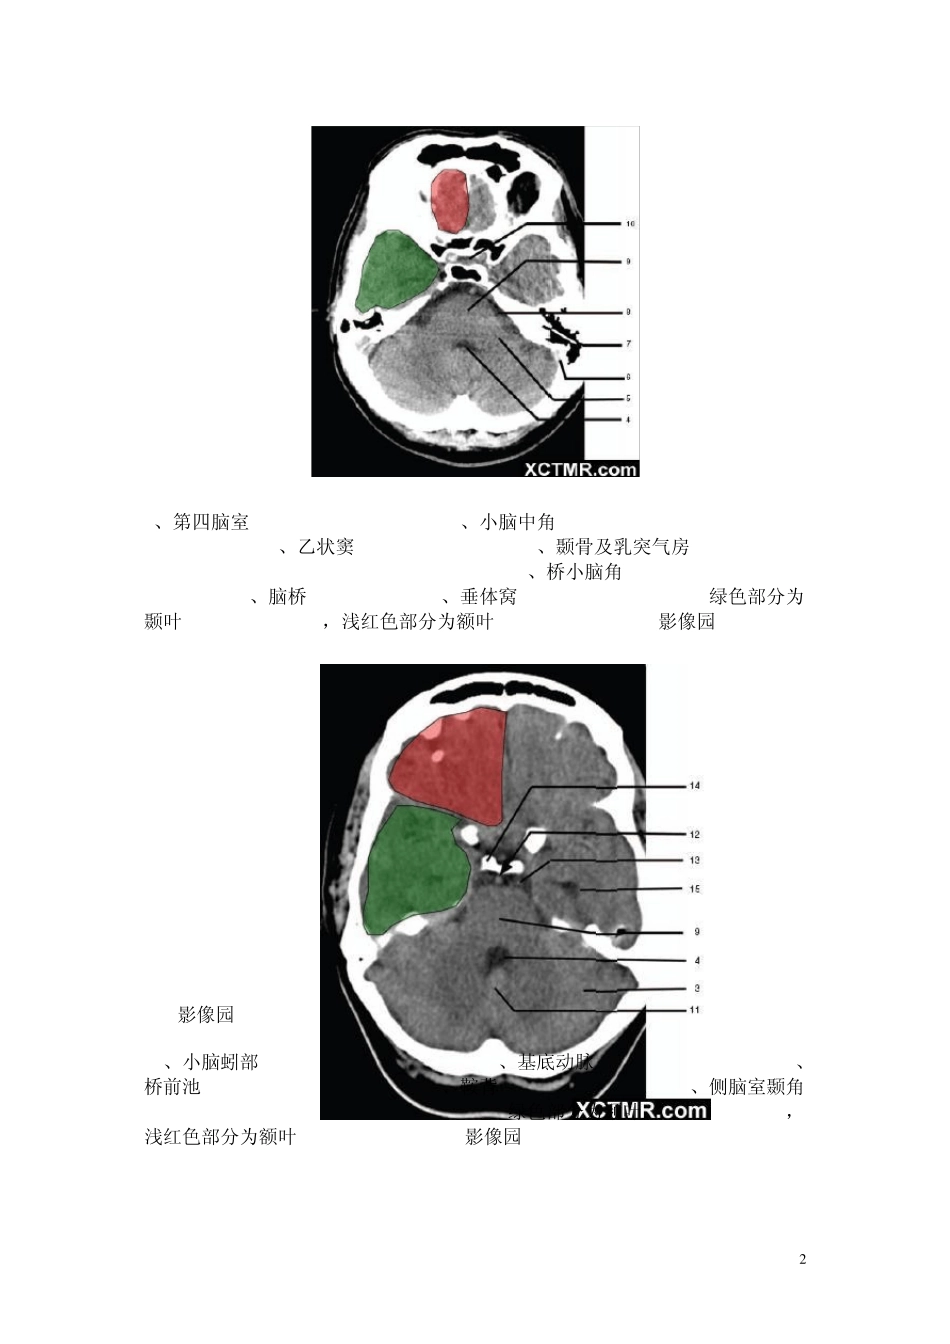

1 颅脑CT解剖(图文) skC影像园XCTMR.com 1、蝶窦(Sphenoid sinus) 2、延髓 (Medulla oblongata) 3、小脑 (cerebellum) 绿色部分为颞叶(Temporal Lobe),浅红色部分为额叶(Frontal Lobe)skC影像园XCTMR.com skC影像园XCTMR.com skC影像园XCTMR.com 2 4、第四脑室(Fourth ventricle) 5、小脑中角(Middle cerebellar peduncle) 6、乙状窦(Sigmoid sinus) 7、颞骨及乳突气房 (Petrous temporal bone and mastoid air cells) 8、桥小脑角(Cerebellopontine angle) 9、脑桥 (Pons) 10、垂体窝(Pituitary fossa) 绿色部分为颞叶(Temporal Lobe),浅红色部分为额叶(Frontal Lobe)skC影像园 XCTMR.com skC影像园 XCTMR.com 11、小脑蚓部(Cerebellar vermis) 12、基底动脉(Basilar artery) 13、桥前池 (Prepontine cistern) 14、鞍背 (Dorsum sellae) 15、侧脑室颞角(Temporal horn of lateral ventricle) 绿色部分为颞叶(Temporal Lobe),浅红色部分为额叶(Frontal Lobe)skC影像园 XCTMR.com 3 skC影像园XCTMR.com 16、环池 (Ambient cistern) 17、角间池 (Interpeduncular cistern) 18、大脑角 (Cerebral peduncle) 19、侧裂池 (Sylvian fissure) 绿色部分为颞叶(Temporal Lobe),浅红色部分为额叶(Frontal Lobe) skC影像园XCTMR.com 4 skC影像园XCTMR.com 20、小脑上池 (Third ventricle) 21、侧脑室前角 (Frontal horn of lateral ventricle) 21a、第三脑室 (Third ventricle) 绿色部分为颞叶(Temporal Lobe),浅红色部分为额叶(Frontal Lobe),黄色部分为枕叶(Occipital Lobe)skC影像园XCTMR.com 5 skC影像园XCTMR.com 22、尾状核头部 (Head of caudate nucleus) 23、岛叶 (Insular cortex) 24、外囊 (External capsule) 25、豆状核(Lentiform nucleus) 26、丘脑(Thalamus) 绿色部分为颞叶(Temporal Lobe),浅红色部分为额叶(Frontal Lobe),黄色部分为枕叶(Occipital Lobe)skC影像园XCTMR.com 6 skC影像园XCTMR.com 27、纵裂 (Interhemispheric fissure) 28、内囊前肢 (Anterior limb of internal capsule) 29、内囊膝部 (Genu of internal capsule) 30、内囊后肢(Posterior limb of internal capsule) 31、侧脑室三角区及脉络丛钙化(Trigone of lateral ventricle and calcified choroid plexus)...